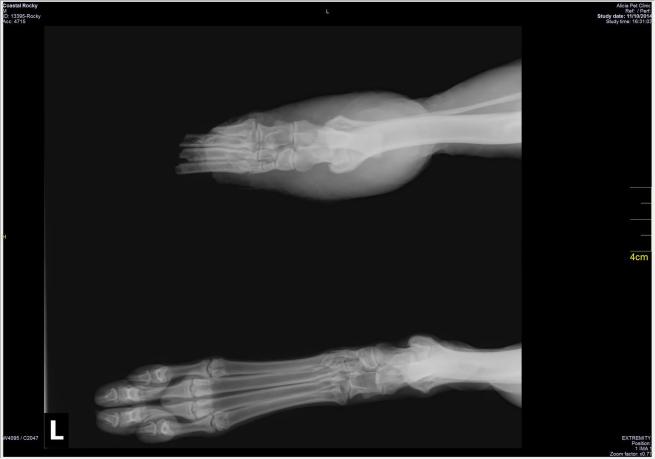

Rocky doveva essere operato con urgenza: non c’era altro da fare che amputare la zampa. L’operazione però costava 2.500 dollari e così è scattata la gara di solidarietà sul web: i fondi necessari sono stati raccolti, Rocky è stato operato e ora sta bene.

Sulla pagina Facebook dell’organizzazione sono state postate le foto di Rocky prima e dopo l’amputazione: “Considerando tutto quello che ha passato, penso che se la caverà alla grande”, ha raccontato la veterinaria Maria Bromme.